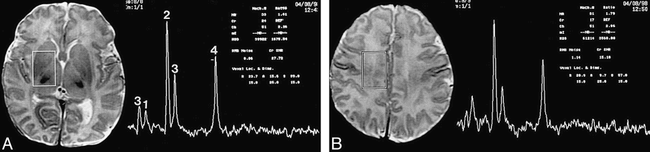

Location of voxels and normal neonatal proton spectra.

A, The deep gray nuclei voxel includes most of the lentiform nucleus, the ventrolateral thalamus, and the posterior limb of the internal capsule. The spectrum reveals: 1) a small myoinositol peak, 2) a large choline peak, 3) two small creatine/phosphocreatine peaks, and 4) a medium-sized NAA peak.

B, The watershed voxel includes primarily white matter from the intravascular boundary zone. Note that the NAA and choline peaks are relatively smaller in the less mature watershed zone than in the more mature deep gray nuclei. Minimal or no lactate was seen in most patients who were developmentally normal at 12 months.